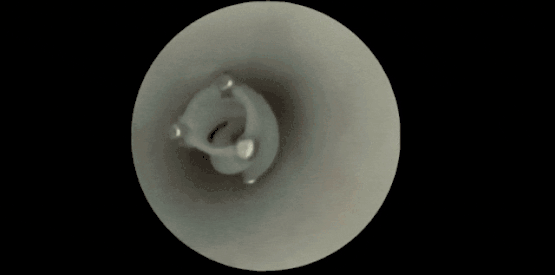

这一次,团队保留了其中最关键的结构——螺旋状的侧翼、中空的管道和开槽的外壁,并将原本指甲盖大小的装置缩小到了直径与长度仅几毫米,恰好适合在直径3~5毫米的大脑血管中穿行。

机器人进入血管后,外部施加的旋转磁场会驱动它快速旋转。特殊的中空设计使得它在前进时会产生负压,液体从前端吸入,再从后端和侧槽喷出,从而推动机器人前行。

实测结果显示,这种机器人能以每秒23厘米的速度,在动脉血流速度下灵活穿梭。赵芮可指出:“我们能轻松让它达到这一速度,但23厘米/秒并非上限。只要继续提高磁场的旋转速度,它的速度甚至能达到60厘米/秒。”

机器人的特殊结构,使其能在血管中快速前进 | 参考文献[2]